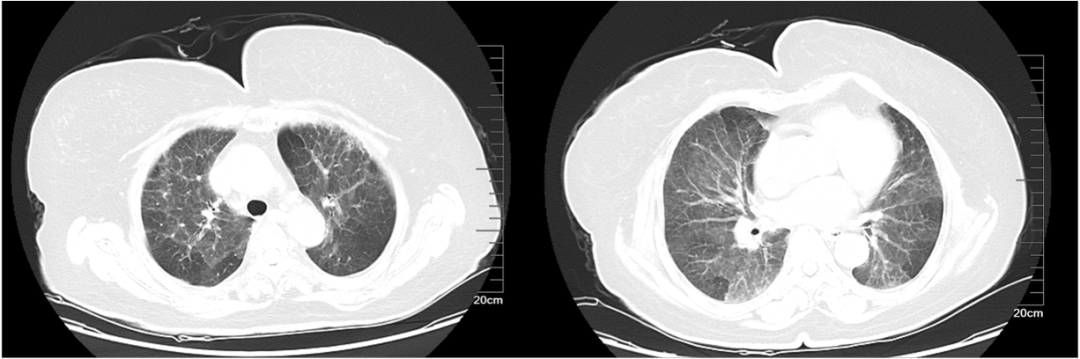

过敏性肺炎1例

• 女,65岁

• 主诉:反复胸闷气喘1年

• 现病史:现病史:患者一年前无明显诱因下出现胸闷、气喘,位于心前区,自觉压迫感,休息后缓解,伴活动后气喘,爬2楼气喘明显,无胸痛,无畏寒发热,患者症状改善不明显。

• 检查日期:2019/08/31

影像学表现